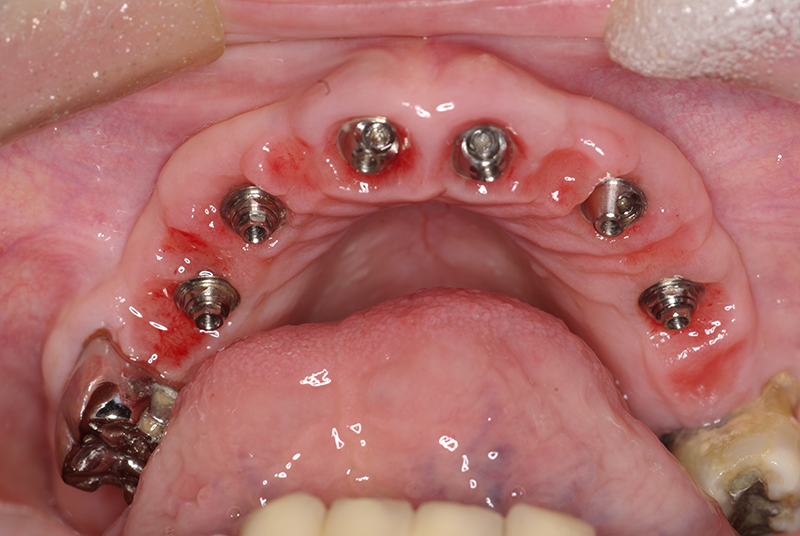

Na Clínica Pontes Odontologia, somos referência em implantes dentários em Fortaleza, oferecendo tratamentos de alta qualidade e tecnologia de ponta. Os implantes dentários são estruturas de titânio posicionadas cirurgicamente no osso maxilar ou mandibular para substituir as raízes dos dentes ausentes. Essa técnica permite a fixação de próteses personalizadas, restaurando a função mastigatória, a estética e a autoestima dos nossos pacientes.

Utilizamos a tecnologia CAD CAM, um sistema avançado que possibilita a confecção precisa das próteses dentárias diretamente sobre os implantes. Esse método inovador garante um ajuste perfeito, um resultado estético superior e proporciona muito mais conforto e durabilidade. Com o CAD CAM, nossos pacientes contam com um processo mais rápido e previsível para alcançar o sorriso desejado.